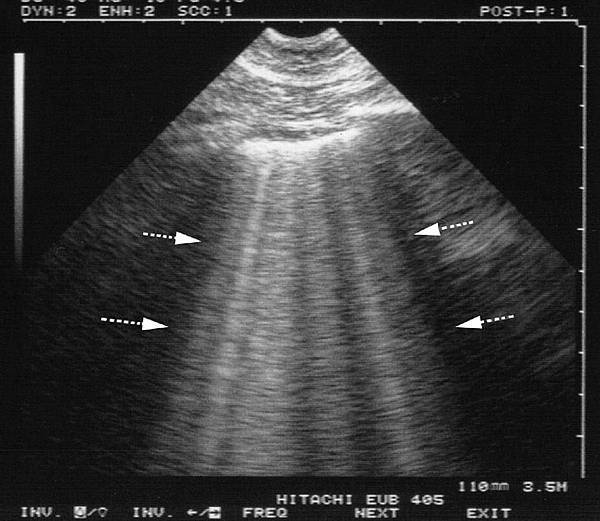

Lung echo

POCUS :

Acute lung edema

> 3 B-lines per rib space